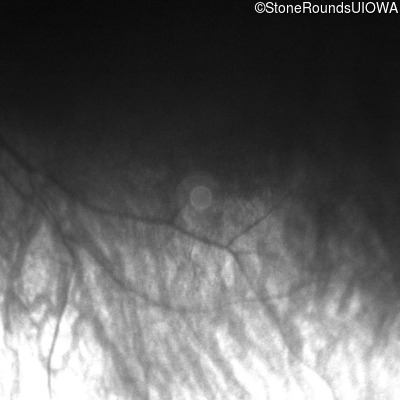

Infrared Fundus Photograph - Right -

No Light Perception

Exemplar

Infrared Fundus Photograph - Left -